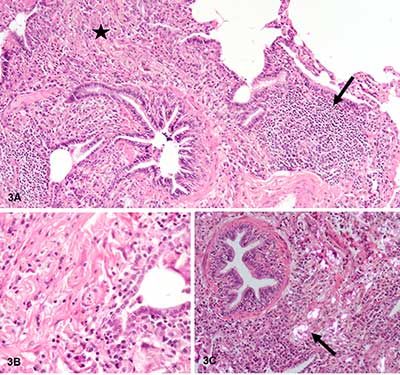

Figure 3

Important non-caseating granulomatous interstitial inflammation, with lymphocytes (black arrow Figure 3A), numerous macrophages and multinuclear giant cells, sitting preferentially in peribronchiolar regions (black star Figure 3A, B). The granulomas contain characteristic needle-shaped birefringent crystalline material in polarized light (black arrow Figure 3C).